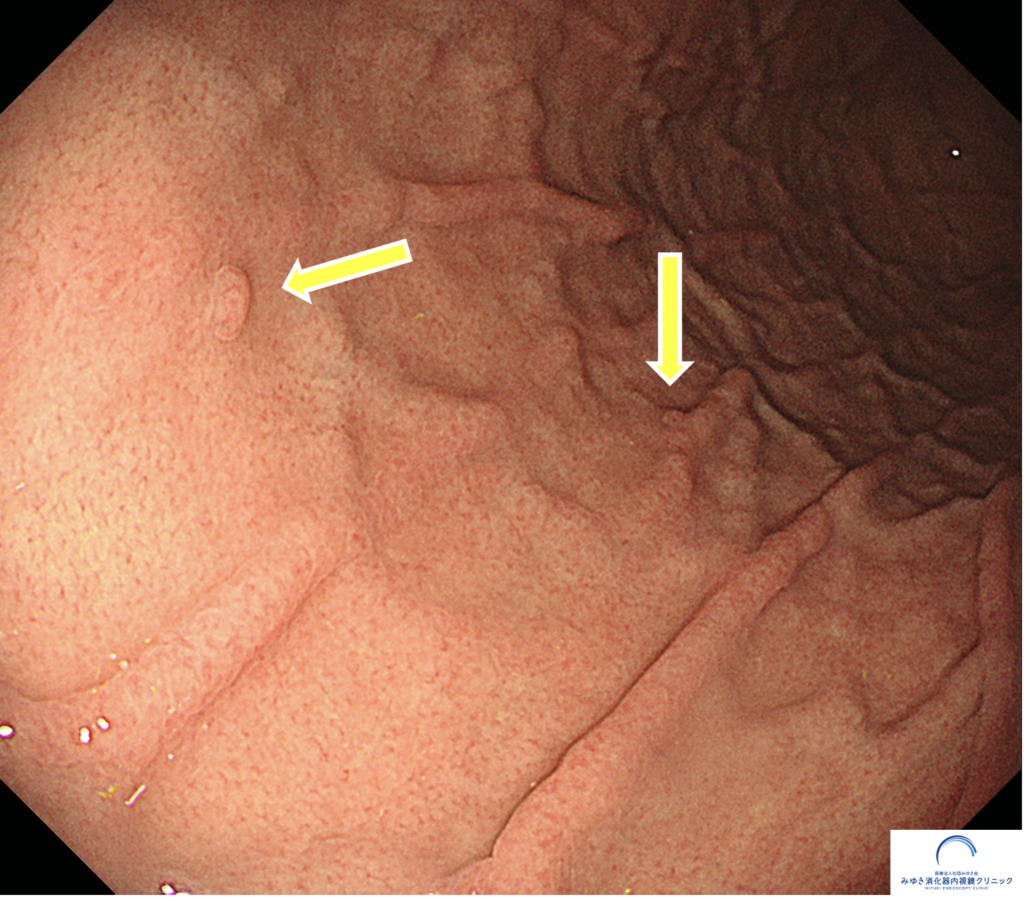

当院で行った胃カメラ検査では、正常な胃粘膜は全体的にきれいで、正常な胃粘膜と考えられる所見でした。胃体部にはRAC(ラック)が明瞭に確認でき、ピロリ菌感染を疑う所見は認められませんでした。

② RAC(ラック)

胃体部から胃角部には多数のヒトデ様の発赤点が規則正しく並んでいるのが確認できます。これは「RAC(ラック)」と呼ばれるもので、その正体は胃の粘膜内の血管です。このRACの有無を判定することが非常に大事で、RACが確認できれは95%以上の確率でピロリ菌がいないと判定することができます。